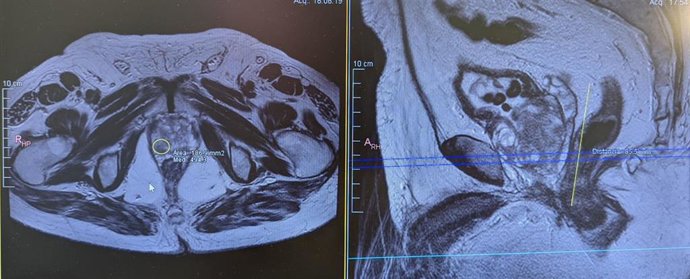

Imagen de bipsia de próstata por fusión

La biopsia de próstata por fusión, que consiste en fusionar la imagen de la resonancia con la ecografía para dirigir la punción hacia las zonas sospechosas. "A pesar de que este procedimiento sea más eficiente, se debe completar con la biopsia sistemática del resto de la próstata", ha concretado el especialista.